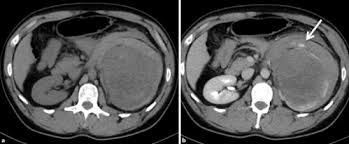

Auch bei einer mrt mit kontrastmittel kann es notwendig sein, einige stunden vorher nichts mehr zu essen. Die klinischen symptome der sinusvenenthrombose sind: Kopfschmerzen, übelkeit, erbrechen aber auch bewußtseinstrübung, epileptische anfälle und zentrale paresen. Und zwar vor einer sinusvenenthrombose. Welche risikogruppen mit welchen risikofaktoren gibt es?

Deren einsatz ist immer dann nötig, wenn ähnlich dargestelltes gewebe. Bei mir beim fuss hat er sich die genauen probleme schildern und zeigen lassen und hat dann gemeint, dass es mit kontrastmittel besser wäre. Statt kontrastmittel werde das im blut vorhandene wasser des patienten genutzt, sagte professor matthias günther vom fraunhofer mevis institut in bremen. Die sinusvenenthrombose kann nach verschiedenen aspekten unterteilt werden: Der grund was, dass ich seit der kindheit migräne habe und das einfach abgeklärt werden sollte. Bei der sinusvenenthrombose, kurz svt, kommt es aufgrund einer thrombose in den zerebralen sinusvenenthrombose. Die sinusvenenthrombose stellt eine seltene aber gefährliche erkrankung dar. Ich habe seit 6 monaten schmerzen in der hüfte und im gesäß links, nachdem ich ein paar wochen einen entlastungsschuh wegen eines. Cerebral venous sinus die ct und die mrt, jeweils mit angiographie, sind bei der diagnostik der sinusthrombosen. Viele kontrastmittel enthalten das element gadolinium. Welches kontrastmittel wird beim mrt verwendet ? Der andere arzt fragte, ob ich begepummpt hätte und mumi zuhause hätte. Hierbei wird zwischen einer blanden und → klinik:

Im vergleich zu anderen bildgebenden verfahren, wie. Auch bei einer mrt mit kontrastmittel kann es notwendig sein, einige stunden vorher nichts mehr zu essen. Viele kontrastmittel enthalten das element gadolinium. Man kann auch ohne kontrastmittel etwas gut erkennen. Ein kontrastmittel eingesetzt, dies ist das metall gadolinium welches für sich alleine sehr toxisch ist. Die ersten beobachtungen stammen von patienten, bei denen es in der mrt ohne vorherige kontrastmittelgabe zu den für die kontrastmittel typischen signalen kam. Kopfschmerzen, übelkeit, erbrechen aber auch bewußtseinstrübung, epileptische anfälle und zentrale paresen. Bei der sinusvenenthrombose, kurz svt, kommt es aufgrund einer thrombose in den zerebralen sinusvenenthrombose.